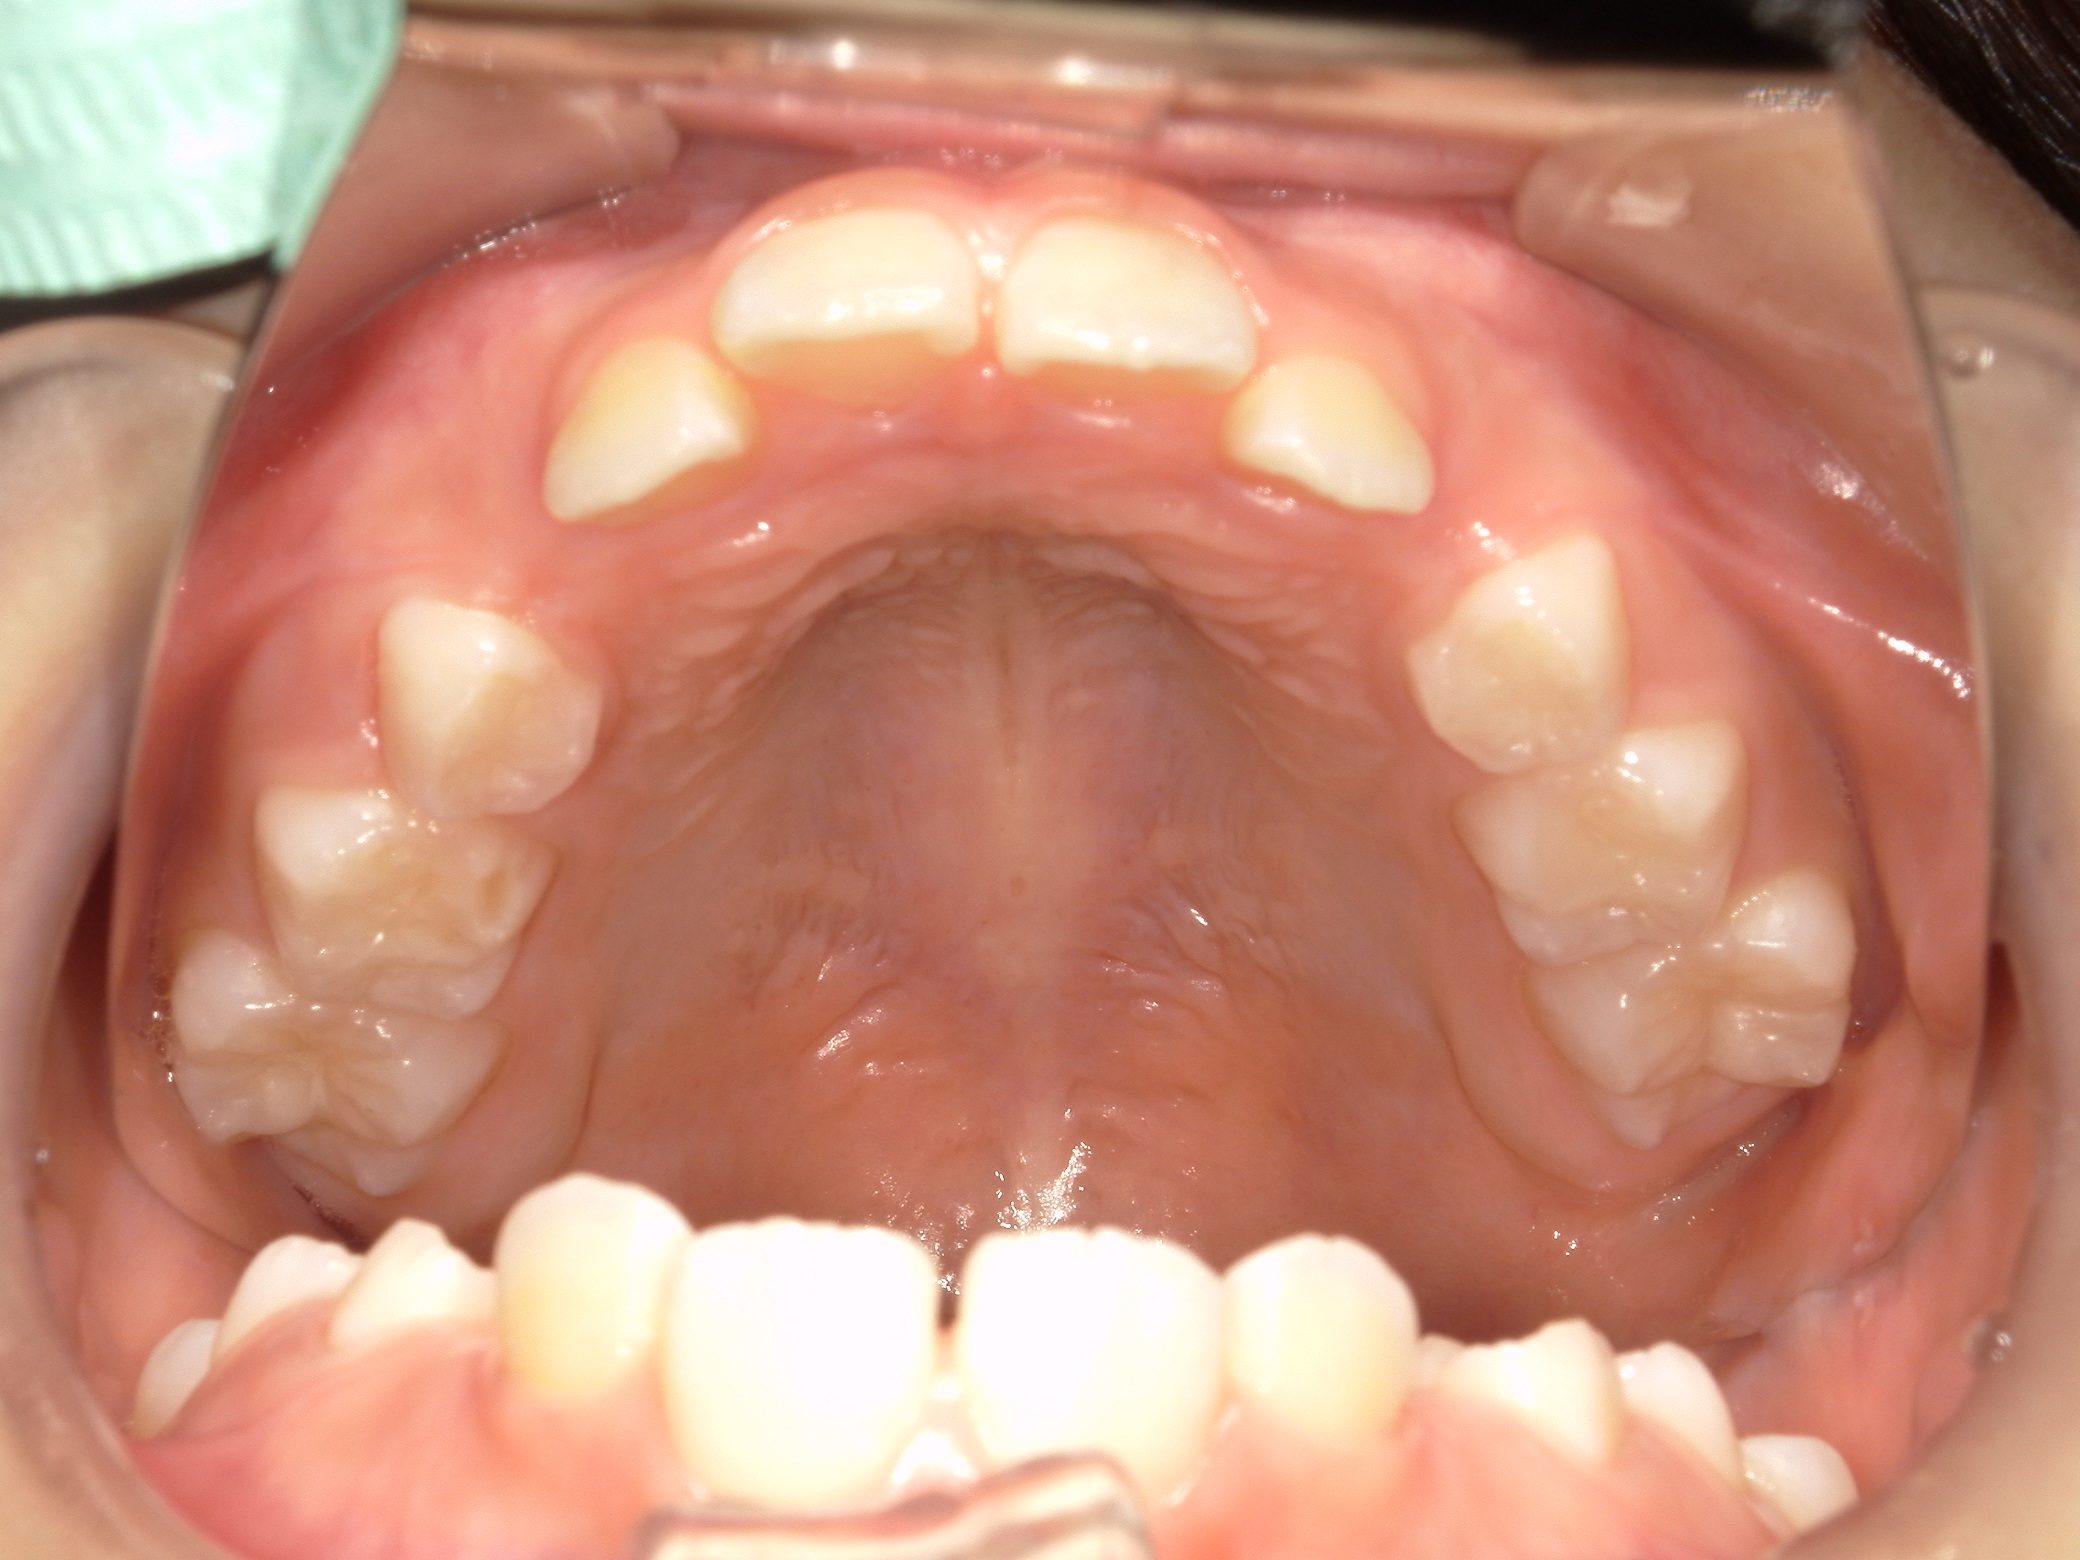

【小学生】マイオブレース矯正 上顎前突(出っ歯)と叢生(でこぼこ)を改善

小学生で開始

マイオブレース

でこぼこ

出っ歯

過蓋咬合

非抜歯

1期治療のみで改善

Before

After

治療期間

1.5年

治療開始

8歳

種類

マイオブレース矯正

使用装置

機能矯正装置 3Dリンガルアーチ

コメント

とてもきっちり取り組んでくれたのでスムーズに治りました。

終了して数年たちますが、現在もしっかり維持してくれています。